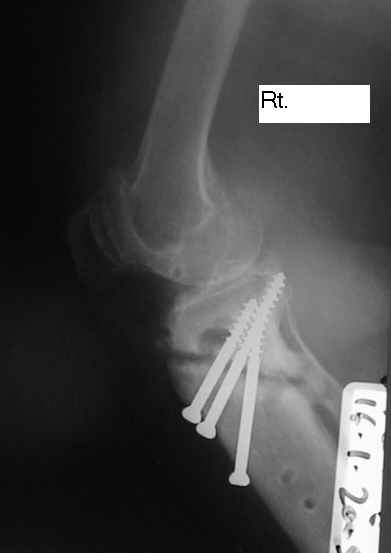

Dorogie Kollegy,Ko mne obratilas' bol'najia, ei 64 goda, ona stradaet ot dvuhstoronnego varusnogo gonoartroza, ei bila vipolnena Visokajia Ostotomjia goleny sprava 01.06.2004, zona osteotomii ne sroslas', plastina bila udalena 12.09.2004 (vidimo iz-za ee nestabilnosti), zona osteotomii tibia bila fixirovana 3-mjia shurupami. Seachas sylno bespokoyat boly v dvuh sustavah, hodit s trudom s pomoshyu Walker, a voobshe ona seachas na invalidnoi kolyaske. Podzkazite, pozhalusta, kak mozno ei pomoch' (snimky prilagayutsa)

Уважаемый Dr.Castro. Мне кажется возможной причиной несращения перелома явилось затекание синовиальной жидкости в зону остеотомии. Проксимальный фрагмент б.берцовой кости мал и "неудобен" для фиксации. Как вариант - можно предложить ЧКДО по Илизарову с временной фиксацией н.з бедра с целью усиления стабильности.Но с аппаратом придется повозиться ( поиграть фрагментами голени).Если нет возможности или желания заниматься аппаратом, придется выполнить СТАБИЛЬНЫЙ остеосинтез мыщелковой или г-образной пластиной, но обязательно с аутопластикой области несращения. Или в виде аутокрошки, или путем перемещения костного трансплантата с дистального фрагмента б.берцовой кости кверху с перекрытием области несращения.

Уважаемый Dr.Castro, я абсолютно согласен с коллегой на счет первого варианта. Использовать пластину с угловой стабильностью не советую поскольку у нас были случаи несращения в этой области при использовании Г-образных пластин после первичного остеосинтеза.В даном случае нужна постоянная и мощная компресия которую можно достичь только методом Илизарова.

U bol'nogo non-union osteotomii tibii. V vozraste 64 let, sdelal bi sleduiezhee:

1. I predpochel bi ego: Total Knee Arthroplasty. Nuzhen budet Revision ( Long stem) tibial Component.

2. Ne sovetuiu delat' geroicheskix postumkov v otnoshenii Non union. Tut est' mnogo problem, ved' esteotomia provedena ne pravili'no s tochki zrenia deformazii. Orientazia ploskosto kollennogo sustava xotia ne ploxa v sagital'noii ploskosti, no vo frontl'noi idet sil;noie otklonenie narozhu i vniz. A nam tida ne nado.